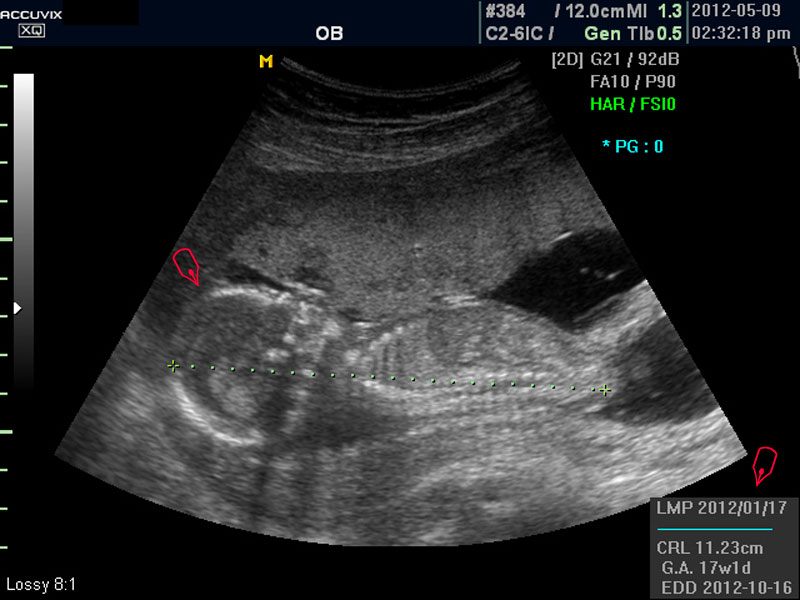

우선 초음파 사진에서 볼 것은 태아의 크기가 정상인가 하는 것입니다.

보통 태아의 발육은 머리부터 엉덩이까지의 크기인 CRL(Crown Rump Length의 약자)이 정상인가 하는 것과 태아의 두상 크기인 BPD(BiParietal Diameter의 약자)가 정상 범위에 들어 있는가 하는 것으로 판단합니다.

화면에서 좌측이 태아 머리 부분으로 빨간 펜으로 표시되어 있습니다.

초음파 상 태아의 머리가 좌측인가 우측인가 하는 것은 초음파 탐촉자의 위치를 어디에 두었느냐에 따라 다른 것 뿐으로 화면상 어디 위치하는 지는 중요하지 않습니다.

또한 이 시기는 태아의 크기가 양수에 비하여 아직 작기 때문에 자궁 내에서 하루에도 수십번 이리저리 방향을 바꾸는 시기이기 때문에 위치는 큰 의미가 없습니다.

모든 사진에서 우측 하단에는 기본적인 발육 정보가 기록되는데 세번째 사진에서 빨간 펜으로 표시한 부분이며 그 내용의 의미는 아래와 같습니다.

참고로 이런 측정 수치가 나타나는 양식이나 위치는 초음파 장비마다 다르지만 용어는 대체로 공통된 의학 용어를 사용하기 때문에 대동소이합니다.

1. LMP

Last Menstrual Period의 약자로 최종 월경일입니다. 이런 최종 월경일을 바탕으로 현재의 임신 주수와 초음파상 측정 지표들간에 얼마나 괴리 되어 있나 하는 것을 판단하는 것입니다.

2. CRL

위에 말한 태아 크기를 말하는 지표로 실제 수치가 표시됩니다.

3. GA

Gestational Age의 약자로 우리말로는 임신 주기라고 하며 CRL이나 BPD등을 기준으로 했을때 임신 몇주 며칠에 해당하는 지 나타낸 것입니다.

5.EDD

Estimated Due Date의 약자로 초음파 측정치를 바탕으로 산출한 출산 예정일입니다.